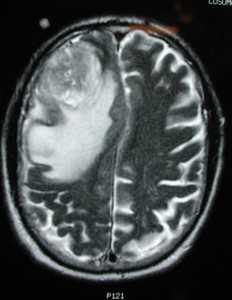

МРТ того же пациента. Т2-взвешенное изображение демонстрирует то же поражение, что и на предыдущем рисунке с заметным отеком и смещением срединных структур. Эти находки соответствуют высокой степени злокачественности опухоли.

Как выглядит глиобластома на МРТ? Как правило, образование на томограммах представляет собой зону, имеющую в основном пониженный сигнал на Т1-взвешенных изображниях и повышенный сигнал на Т2- взвешенных изображениях. Могут присутствовать внутренние кистозные участки, участки потери сигнала, обусловленные крупными сосудами, внутренние зоны повышенной интенсивности сигнала на Т1-ВИ (геморрагические очаги), новообразованные сосуды, очаги некроза, обширный перитуморозный вазогенный отеком и значительный масс-эффект. Также может выявляться неравномерное, но интенсивное накопление контрастного вещества на основе гадолиния (та же картина наблюдается на КТ после введения йодсодержащего контраста), как в основной опухоли, так и в метастатических очагах, характерных для МФГ. МРТ более чувствительна к этим изменениям, чем КТ.